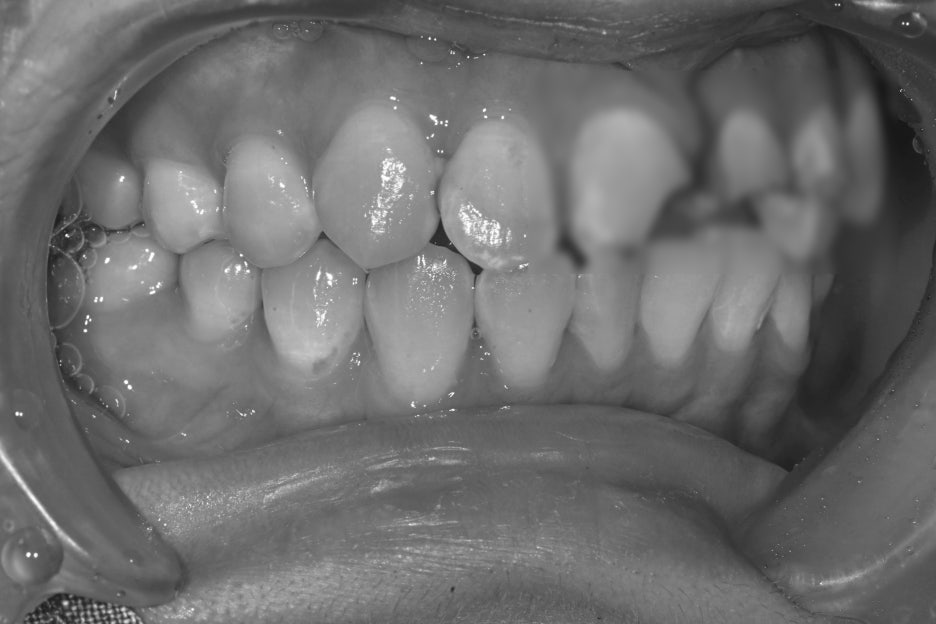

치료 전 후 사진

치료전, 치료후 사진